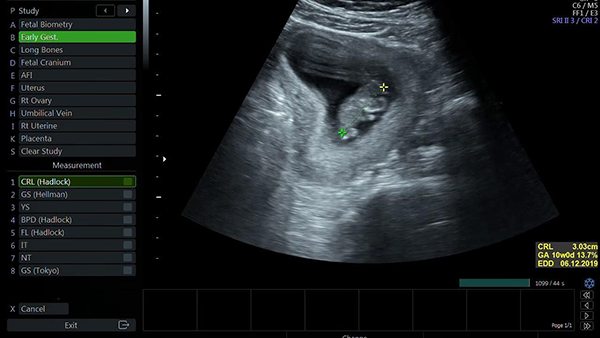

+ CRL (Crown rump length): Bạn có thể biến được chiều dài đầu mông của bé thông qua chỉ số này, thông thường thì nó sẽ dao động từ 31 mm đến 40 mm.

Khi nhìn kết quả siêu âm, nhiều ba mẹ vẫn cảm thấy mơ hồ không biết con mình có thật sự khỏe mạnh hay không. Dưới đây là một số chỉ số tiêu chuẩn cho thai nhi 10 tuần tuổi để ba mẹ có thể tham khảo:

Chỉ số về mặt kích thước

Nế thai nhi phát triển khỏe mạnh thì chỉ số cân nặng của bé sẽ rơi vào khoảng 4g, kích thước đo từ đầu cho tới mông là khoảng 3.1cm. Trong giai đoạn này chân bé có thể di chuyển và bé biết cách sử dụng nước ở màng ối.